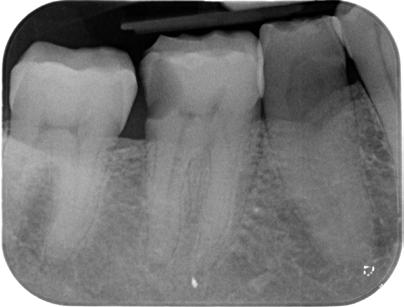

1. ábra: Kiindulási röntgen. A felső nagyőrlőfog trepanálását akut beavatkozásként egy másik rendelőben végezték.

Az endodonciai ellátás a trepanációs nyílás kialakításával kezdődik. Ez a lépés biztosítja a gyökércsatorna bemeneti nyílások könnyű lokalizál-

hatóságát, a csatornák kézi tűkkel való szondázhatóságához szükséges megfelelő hozzáférést, valamint a gyökércsatornák feltágításához, tisztításához és a gyökértömés elkészítéséhez szükséges kiindulási

feltételeket. A trepanációs nyílás kialakítására vonatkozó szabályok meghatározzák, hogy ez a nyílás milyen formával és mérettel kerül kialakításra, valamint azt is, hogy a gyökércsatorna-bemenetekhez képest hol helyezkedik el. Ez a kezdeti fázis jelentős mértékben meghatározza az ezt követő lépések lehetséges sikerességét. Kijelenthető, hogy az endodonciai ellátás sikeressége nagymértékben függ a trepanációs nyílás megfelelő kialakításától [1–3]. Ha a trepanációs nyílás nem megfelelő pozícióban, mélységben, vagy kiterjedésben kerül kialakításra, akkor az ezt követő terápiás lépések során joggal számíthatunk komplikációk megjelenésére. Megnehezíthetik, vagy bizonyos helyzetekben lehetetlenné tehetik a gyökércsatorna-bemenetek lokalizálhatóságát, a csatornák mechanikai tisztítása során a nikkel–titán (Ni–Ti) gyökérkezelő tűkben fraktúrák kialakulásához vezető nagyságú erők ébredhetnek, sőt akár a megmaradt dentinállo -

2. ábra: A hozzáférési nyílás kialakítása során túlzott mértékű ép foganyag eltávolítása történt mesiobukkális és apikális irányba.

– 3. ábra: A visszamaradt nagy méretű pulpakő teljes mértékben elzárja a palatinális csatornabemenetet. – 4. ábra: A gyökértömés behelyezése előtt látható állapot. A csatornák feltágítása és tisztítása befejeződött.

mány kritikus mértékű strukturális károsodását is okozhatják (1–5. ábrák). Egészen a közelmúltig annak a fontosságát hangsúlyozták, hogy a trepanációs nyílások kiterjedésének kellően nagynak kell lennie ahhoz, hogy a kézi és gépi eszközök számára közvetlen, egyenes vonalú hozzáférést biztosítsanak a gyökércsatornákba való behatolás során. Az utóbbi években viszont a minimálinvazív módon kialakított trepanációs nyílások (ultrakonzervatív üregek, ninja hozzáférés stb. …) [4] előnyeire fókuszáló szemléletek kaptak egyre nagyobb nyilvánosságot.